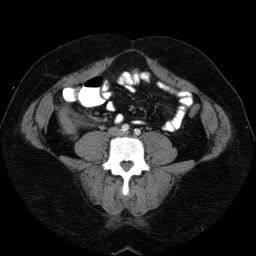

These are images from a contrast enhanced abdominal CT.

Fluid in the right paracolic gutter, and a thickened, inflamed appendix with thickening of the adjacent cecal wall.

Differential: Acute appendicitis is by far the most likely diagnosis.

No appendicolith is seen in this case.

The appendix is normally less than 7 mm in diameter, or if fluid filled, the wall can be up to 3mm thick. This appendix is distended, and the adjacent stranding and fluid indicates the inflammatory process which is causing peritoneal irritation and pain. Here is a series of images showing a normal appendix using similar technique. Note the thin walls of the normal appendix.